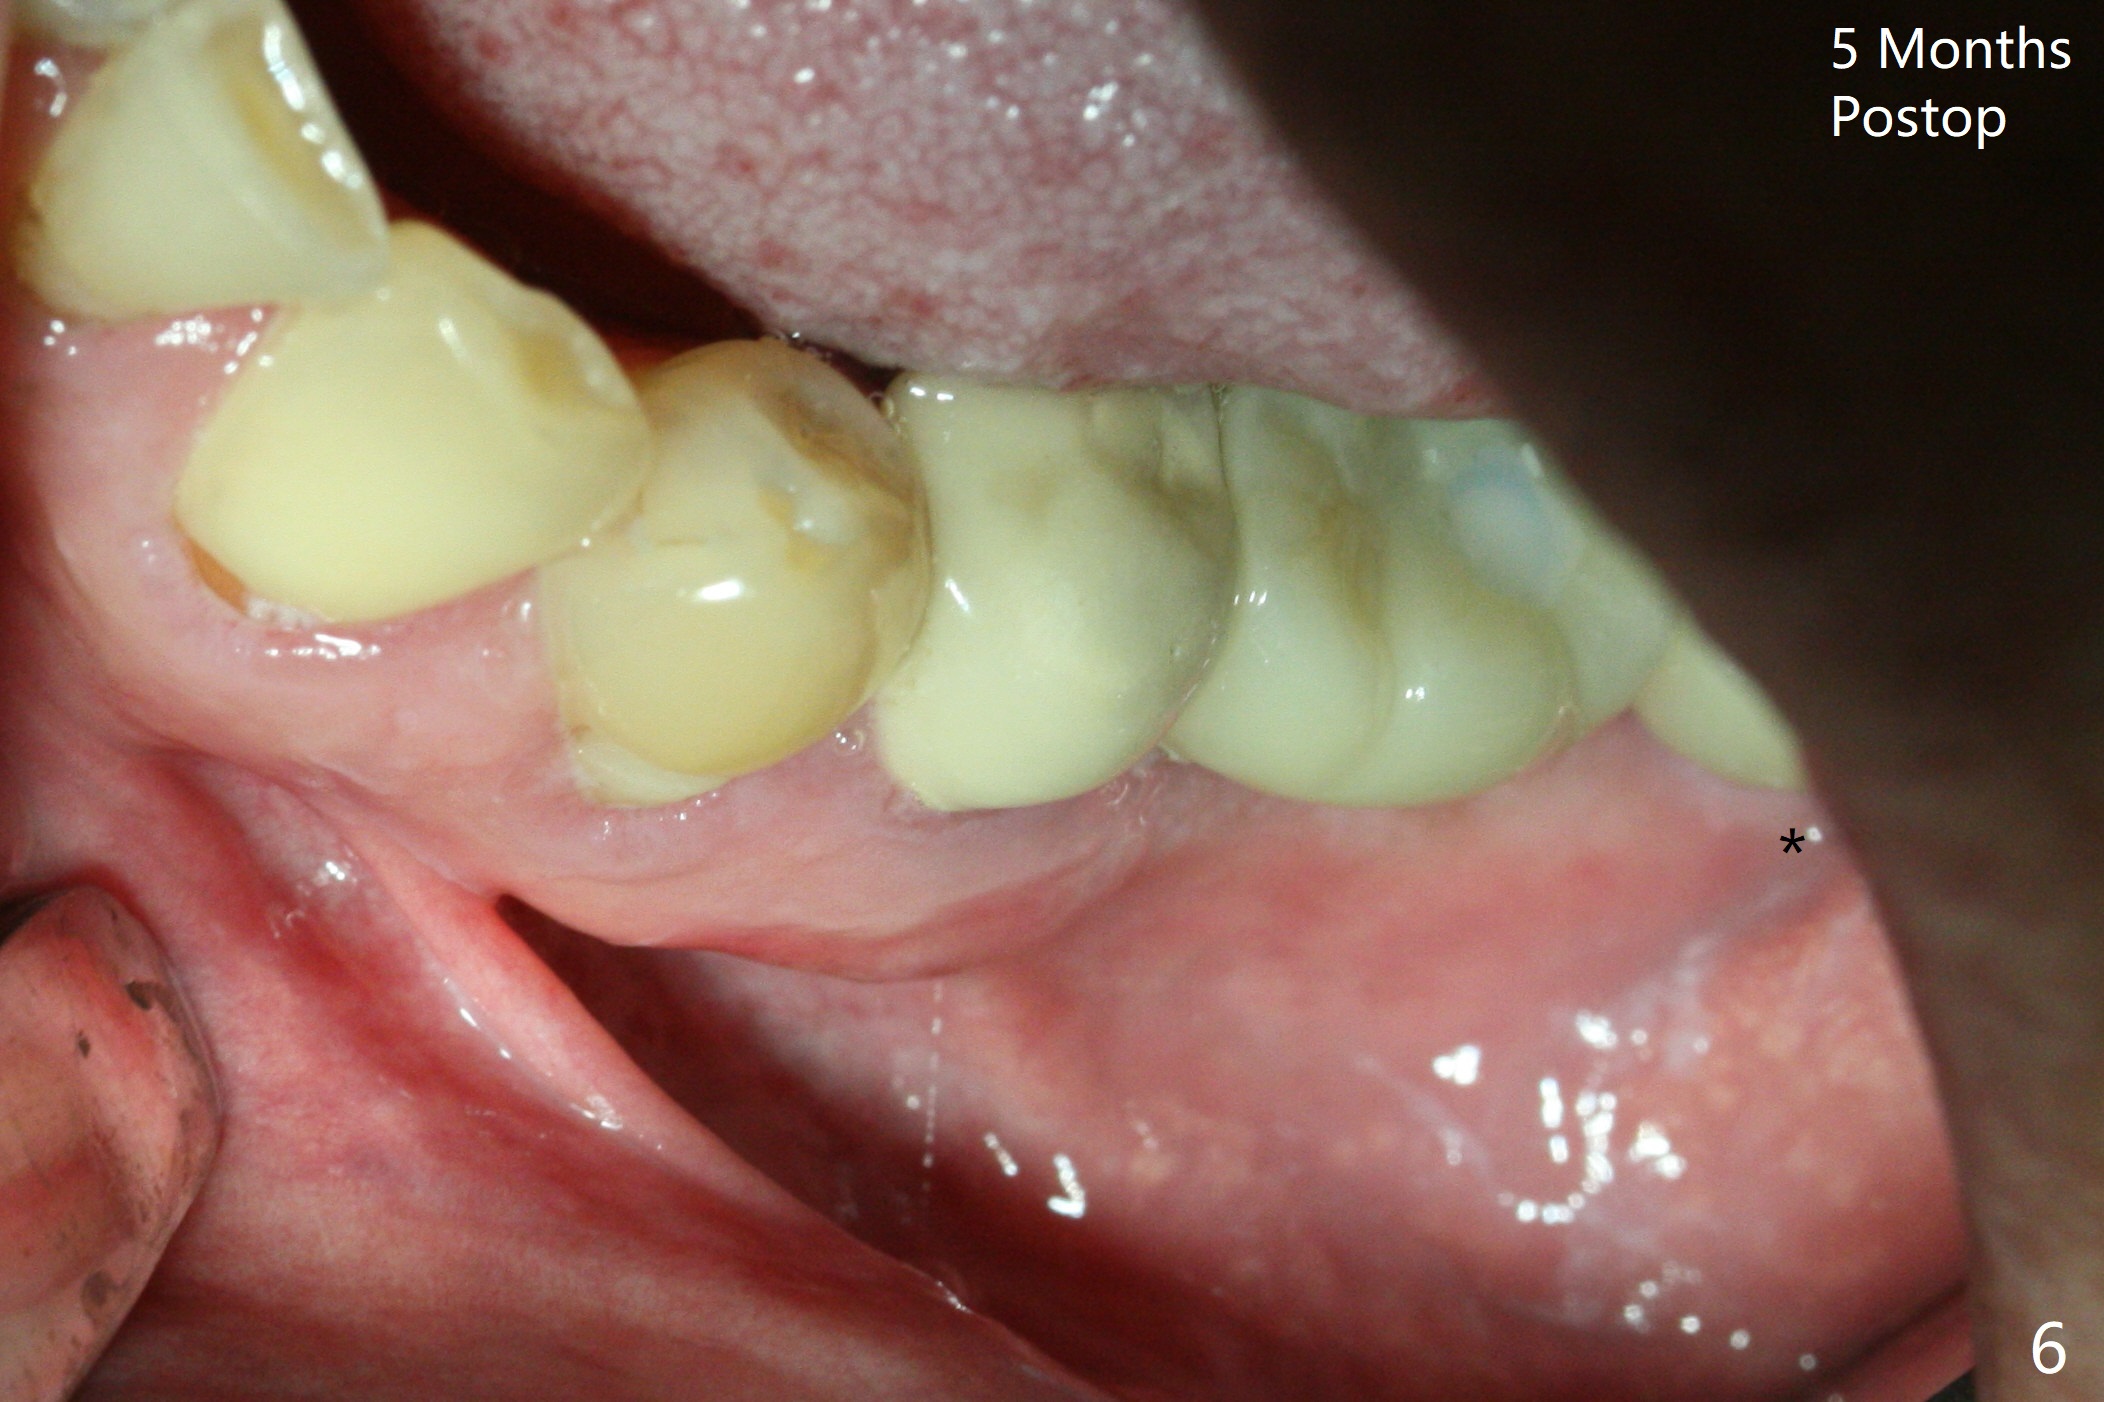

A drawback of placing an implant in the distal socket of the 2nd lower molar is closer to the Inferior Alveolar Canal. The implants seem to have osteointegrated 4.5 months postop (Fig.5). While the ridge at #19 appears to be wider than preop (as compared to Fig.1), that at #18 seems to be atrophic 5 months postop (Fig.6 * (1 week post cementation)). The distal implant placement at #19 may increase possibility of abutment screw loosening during functioning (Fig.7 *). When the patient returns for periodic exam 1.5 months post cementation, loose contact between the implant crowns is noted (Fig.8). The bony trabeculae form between the 2 implants crestally 12 months postop, i.e., 7 months post cementation (Fig.9). The loose contact between the 2 implants is corrected 14 months post cementation.